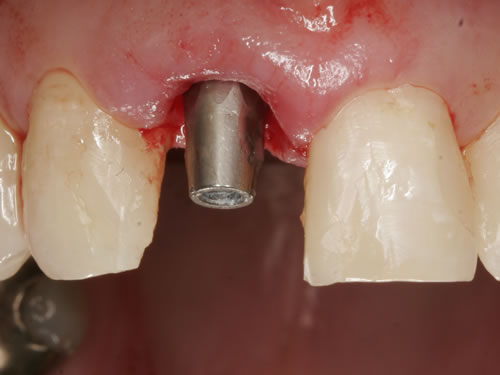

In einigen Fällen werden die Implantate am gleichen Tag wie die Entfernung der Zähne eingesetzt. Man spricht dann von einer Sofortimplantation (Abb. 2.3, 2.4). Wenn die Eingliederung des Zahnersatzes als Stegprothese oder als provisorische Krone innerhalb der ersten 24 Stunden direkt auf den frisch gesetzten Implantaten befestigt wird, dann wird auch von einer Sofortbelastung gesprochen. Für eine Sofortimplantation und Sofortbelastung müssen wichtige Kriterien erfüllt werden. Hierzu zählen ein ausreichendes Knochenangebot in Höhe und Breite, damit ein möglichst groß dimensioniertes Implantat gesetzt werden kann, entzündungsfreie Verhältnisse und eine gute Mitarbeit der Patienten. Wichtig ist auch, dass die Patienten ihre „neuen Zähne“ zunächst nur sehr vorsichtig benutzen, denn bei der Stabilität der neugesetzten Implantate handelt es sich zunächst um eine mechanische Stabilität, die in eine biologische Stabilität umgewandelt wird. Vergleichbar ist ein gebrochener Arm, mit dem man ja auch nicht nach einer Eingipsung sofort Tennis spielen gehen sollte. Aber nach der Knochenbruchheilung wird das Tennis spielen genauso gut funktionieren wie vor der Verletzung. In ähnlicher Weise funktioniert das Einwachsen der Implantate.

Abb. 2.3: Wurzelrest im Kiefer.

Abb. 2.4: Sofortimplantation nach Entfernung des reizlosen Wurzelrestes mit Abdeckschraube verschlossen.

Aus der bekannten Tatsache, dass Knochen- und Weichgewebsverlust nach Zahnentfernungen stattfinden und dass der Verlust grösser ist, je länger die Entfernung des Zahnes her ist, wurde die zeitnahe Implantation überlegt. So kann das Hart- und Weichgewebe durch das neue gesetzte Implantat gestützt und muss nicht zu einem späteren Zeitpunkt ersetzt werden. Für eine Sofortimplantation müssen aber wichtige Kriterien erfüllt sein. Hierzu zählen entzündungsfreier Zahnverlust, gute und dicke Zahnfleischform und keine entzündlichen Veränderungen des Zahnhalteapparates. Wenn diese wichtigen Parameter erfüllt sind, dann ist eine Sofortimplantation möglich. Leider sind die Voraussetzungen nur in sehr wenigen Fällen so, da selten gesunde, entzündungsfreie Zähne entfernt werden. In der Bildergalerie wurde ein tief kariöser Zahn ideal entfernt, ein Implantat als Sofortimplantat eingesetzt und mit einer provisorischen Kunststoffkrone versorgt. Nach Abheilung erfolgte die definitive prothetische Versorgung mit einer Vollkeramikkrone (Abb. 7.16, 7.17).

Abb. 7.16: Sofortimplantat eines oberen mittleren Schneidezahnes, mit eingebautem Implantataufbau.

Abb. 7.17: Zementierte definitive Krone nach Einwachsen des Implantates (3 Monate später).